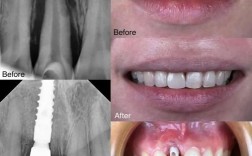

种植牙的原理是通过外科手术将纯钛种植体植入牙槽骨,与骨组织形成“骨结合”,从而支撑牙冠,牙槽骨的密度、高度、宽度是决定种植成功的关键,若患者因长期缺牙导致牙槽骨吸收(常见于缺牙时间超过3个月),可能需要进行植骨、上颌窦提升等辅助手术,增加骨量后再种植。

老年人因长期缺牙、牙周病等原因,牙槽骨吸收往往更严重,可能需要采用数字化导板导航种植、微创种植、即刻种植等技术,或结合骨增量手术(如GBR引导骨再生、块骨移植等)来保证种植体的稳定性,对于牙槽骨条件极差、无法承受传统种植体的患者,还可考虑采用全口/半口即刻负重种植(如All-on-4技术),实现当天种牙、当天戴牙。